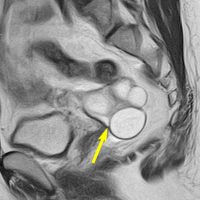

とても小さな腫瘍(微小腺腫) microadenoma

1cm以下の小さなものを微小腺腫といいます。ホルモンを異常に分泌する腫瘍は摘出する必要がありますが,そうでないものは治療の必要がありません。微小腺腫を数年観察しても増大する確率は10%くらいです。逆に,それ以上に大きなものだと,50%くらいの確率で増大します。

日本で汎用されているものでは最も解像力が高い3テスラMRIで撮影された,ガドリニウム増強像です。左側の画像では下垂体の大きさと形は正常に見えます。画像を調整すると,下垂体の内部,右端(黄色の矢印の先)に6mmくらいの小さな腺腫がみつかりました。MRIの性能がよくなったことによって数mmの小さなものも診断できるようになりました。